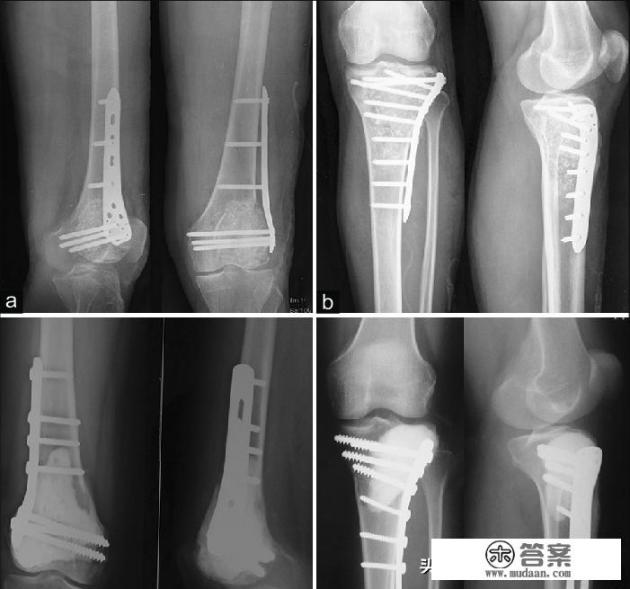

创伤导致的严重粉碎性骨折,出现骨缺损

当骨头受到了强度比较大的暴力损害以后,很有可能发生粉碎骨折,有的时候断端的骨头已经粉碎的,无法给予进行对接。此时可能需要取腓骨的一部分、肋骨的一部分、髂骨的一部分或者是同种异体骨给予进行填补,这种植骨不仅是为了促进骨愈合,还有连接两个骨折断端的重要作用,就相当于在已经无法对接的两个桥梁之间,我们给添加了一小段临时铁轨,这样才能给骨折之间连接、愈合创造机会。

骨不连手术需要植骨

无论是否经过手术,骨折以后都有可能出现骨不连,这种情况多见于患者的身体状态比较差,骨折的折端之间有软组织嵌插阻碍的了血供或者是骨折手术折端之间距离过远等很多因素都可以导致骨不连。

一般情况下,骨折石膏固定或者切开手术术后6~9个月没有骨痂生长既可以判定为骨不连,此时在以往的处置过程当中,一般要给予骨折部位切开,将骨折两端新鲜化,打通闭塞的血管,或者是去除掉阻碍骨折生长的结构比如瘢痕,然而单纯的做这些图纸并不能促进骨折的愈合,在成就骨头的两端,我们需要新鲜的骨质进行补充,而且这些骨质不仅要有骨框架的作用还应该要有骨诱导作用,所以取自体骨植骨是一种比较好的选择。